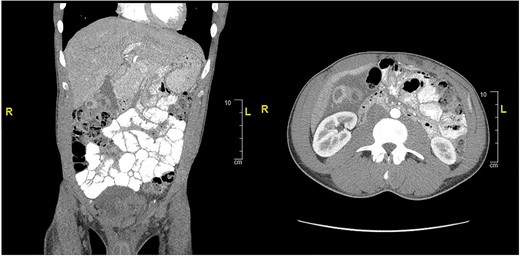

Case presentation #2: A 39-year-old male initially presented with acute cholecystitis (AC) with a markedly thickened wall with abscess formation, not amenable for drainage, treated with antibiotics with improvement, but later experienced recurrent biliary colic symptoms. Repeat computed tomography (CT) imaging (Fig. 4) 2 months later showed a peripherally hyperdense septated collection within the porta hepatis with surrounding fluid signal attenuation; likely representing an abscess seen around the gallbladder possibly secondary to gallbladder perforation due to neoplastic versus inflammatory pathology. Ultrasound showed chronic cholecystitis with cholelithiasis. The patient later underwent elective laparoscopic cholecystectomy. Intraoperatively, extensive adhesions from the liver to the gallbladder and the colon to the gallbladder were noted. The fundus of the gallbladder was densely adherent to the hepatic flexure with no dissection plane. The hepatic flexure felt firm, raising concern of a possible tumor or fistula. The decision was made to remove the right colon en-bloc with the gallbladder. The gallbladder was dissected free in the usual manner and a critical view was obtained. Once the gallbladder was freed, we proceeded with a laparoscopic right hemicolectomy with ileocolonic anastomosis. The specimen was evaluated on the back table; no tumor was seen, but there was what appeared to be an abscess cavity adherent between the gallbladder and colon filled with green stool-colored liquid. The patient tolerated the procedure well and was progressively advanced to regular diet postoperatively and discharged on postoperative Day 3. His final pathology of the operative specimen (Fig. 5) came back as acute on chronic cholecystitis with a micro-fistula between the gallbladder and the adjacent colon.

CT of abdomen and pelvis showing peripherally hyperdense septated collection within the porta hepatis with surrounding fluid signal attenuation likely representing an abscess seen around the gallbladder.